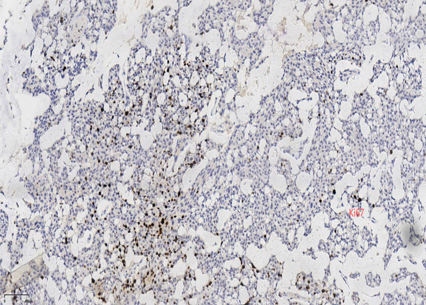

具有神经内分泌表达:CgA、Syn(约70%的比例,阳性细胞表达不等)

CK5/6、CKH-,可斑驳性的残留

肌上皮内-,导管周可-可+